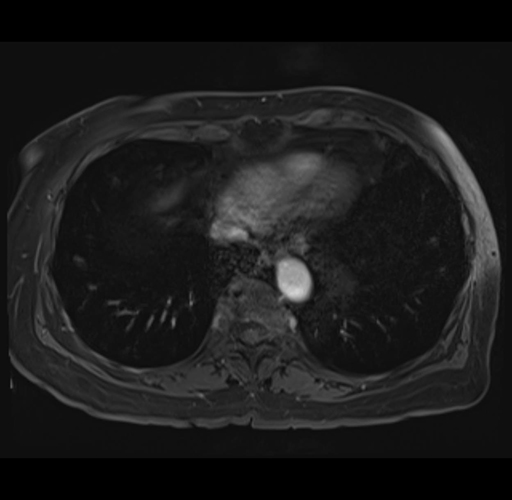

MRI T1